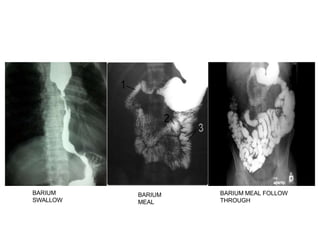

9) Uses:

 barium swallow

 barium meal

 barium meal follow through

 Enteroclysis

 barium enema

BARIUM

SWALLOW

MEAL

BARIUM MEAL FOLLOW

THROUGH